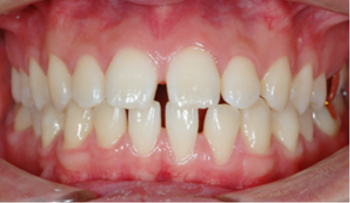

​​​Case 02. 치간공극

치아 사이에 공간이 있는 경우에, 교정 장치를 부착하여 치아 사이에 있는 공간을 뒤로 당겨서 없애게 됩니다.

벌어진 정도와 위치, 교합 관계 등에 따라 양측 또는 편측으로 교정이 들어갈 수 있으며, ​​​​​​​그에 따라 소요되는 기간도 약간씩 차이가 납니다.

교정 치료 Before & After

• 치간공극 교정 치료 전

Before

• 치간공극 교정 치료 후

After